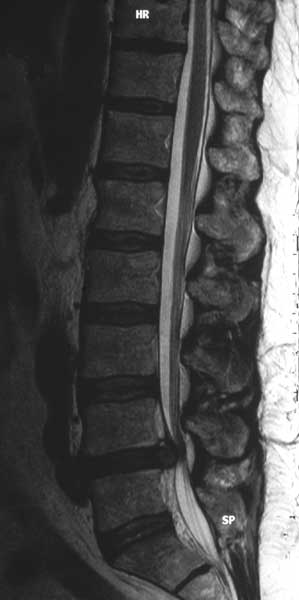

Abb: Mitte, im Kernspinntomogramm